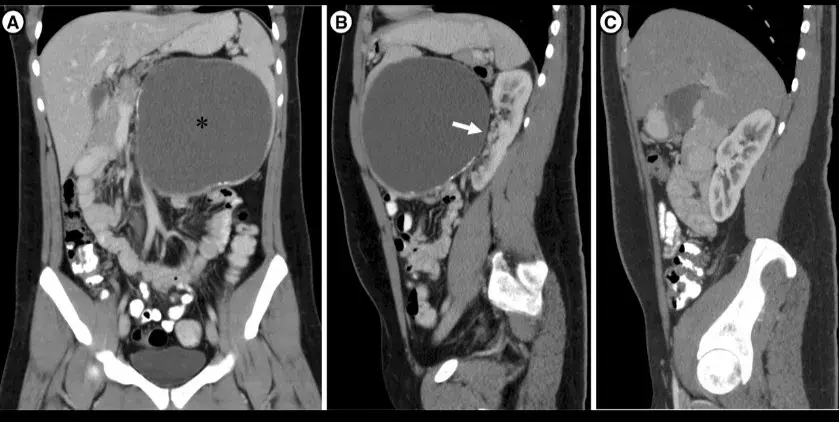

Uma causa incomum de hematúria glomerular intermitente!

Hematúria pós infecção, caso clínicos para auxiliar no entendimento de causas glomerulares comuns e raras...